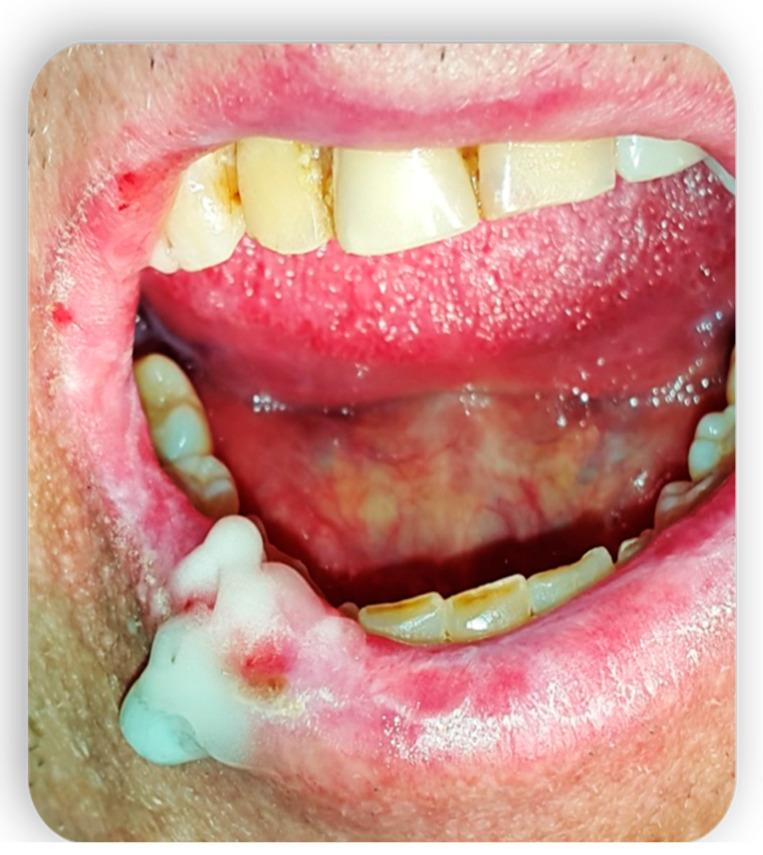

Graft-versus-host disease (GVHD) is a complication of hematopoietic stem cell transplantation (HSCT). GVHD may also develop following solid transplants or blood transfusions if white blood cells are transferred. GVHD affects multiple organs, including the oral tissues. This pictorial review provides a background of GVHD to dental practitioners, describes the most common oral manifestations of GVHD, and highlights the main treatment modifications needed to deliver dental care to patients with GVHD. A narrative review enriched with clinical data was performed by searching the scientific literature for all articles regarding GVHD and oral manifestations/therapies. All articles without exclusion criteria, except animal tests, were included in the above review. Acute GVHD may manifest in the oral mucosa; however, it often develops immediately following HSCT when routine dental treatment is postponed. Chronic GVHD may manifest in the oral mucosa, the salivary glands, and the musculoskeletal compartment. It may indirectly affect the teeth and the oral flora, putting the patient at risk for infections. Importantly, GVHD poses an increased risk for oral cancer. GVHD has a wide range of oral manifestations, some of which may affect dental treatment.